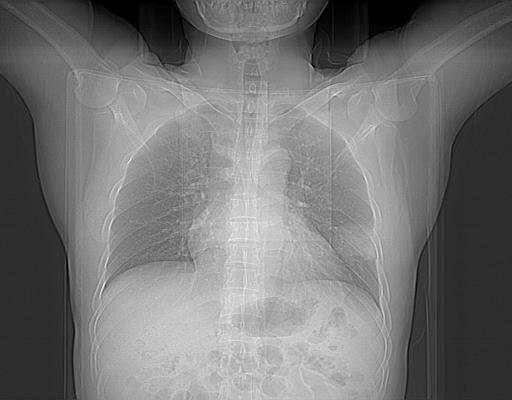

男,38岁,于2009年8月9日晚突发左侧胸痛,今x线提示左下肺阴影,为了明显确诊断,行ct检查,

血常规:嗜酸性细胞增高,单核细胞增高。

病灶发生在下叶,密度均匀,边缘模糊、毛糙,周围血管纹理增强扭曲改变,靠近胸膜处病灶胸膜反应明显。

支持考虑---球形肺炎。

左肺舌叶病变。主体病灶呈类圆形中心密度低,成液化趋势周边班片影分布

考虑肺脓肿

虽然实验室检查支持炎性病变,且病变内有坏死改变(中央呈大片状低密度影),但仍不能掉以轻心,鳞癌也可以有这种影像改变。